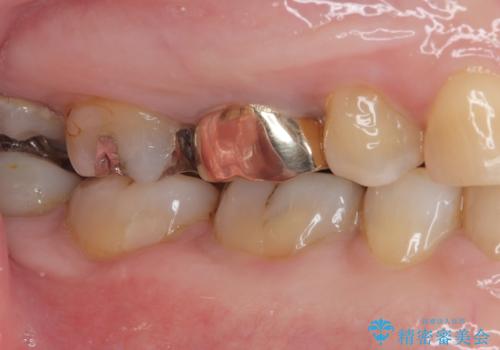

銀歯の下のむし歯 ゴールドクラウンによる補綴治療

- 奥歯で咬んだときに痛みがあり、物が挟まるとのことで来院された患者様です。

咬み合わせが非常に強く、見た目よりも機能と安定性を重視したいとのことで、PGAクラウン(白金加金合金クラウン)にて補綴する治療計画となりました。